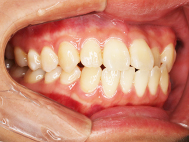

After

| 症状 | 上下前歯叢生 |

| 治療内容 | 上顎部分裏側矯正 下顎は目立ちにくい透明な装置 |

| 治療期間 | 11ヶ月 |

左上の前歯内側に入っている下の前歯ガチャ歯

左上前歯が下の歯の内側に入っているのが気になるとの事で来院されました。目立たない矯正治療を希望しているとのこでした。 上顎の装置は、歯の裏側(リンガル装置)で下顎は表側で矯正治療を行いました。口を閉じた時、上の前歯が内側に入っている為に下の歯を前に押し出している状態でした。その為、上の歯を前に出すだけではその歯が下とのかみ合わせの関係で、前に飛び出すような治療となってしまいます。 今回の症例ではシュミレーションを見て頂き、下の歯も治療し、内側へ下げることによって上の歯も飛びだすことなく、キレイにおさまることを説明し、上下一緒に矯正することをお勧めさせて頂きました。